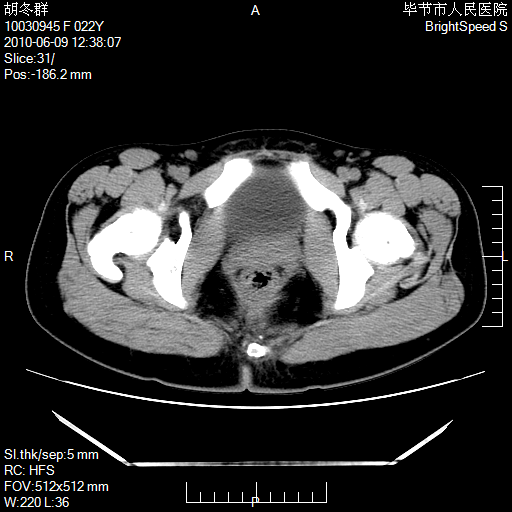

患者23岁,发现腹部包块3月。

左侧卵巢囊腺瘤或囊腺癌

盆腔内囊性占位性病变;考虑左侧卵巢囊腺瘤。

有分隔、壁薄,支持考虑左侧卵巢囊腺瘤。

左侧卵巢浆液性囊腺瘤。

支持考虑左侧卵巢囊腺瘤;宫腔积液。

有分隔、壁薄,支持考虑左侧卵巢囊腺瘤。排尿后,膀胱缩小,由于重力作用,肿块下移就到了膀胱位置,很好理解。